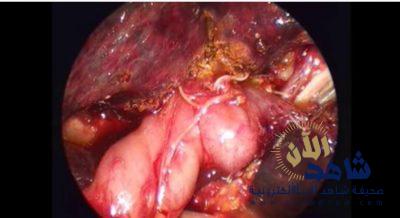

ومن العمليات الجراحية التي تمت عملية إنقاذ حياة طفل يعاني من الم بالبطن بسبب التواء بالامعاء وانتفاخ بالبطن تم استخدام المنظار الجراحي لاستئصال الامعاء وتوصيلها بالمستقيم تكللت بالنجاح .

كما تم مؤخراً إجراء أول حالة رتق قناة صفراويه بجراحة المنظار الدقيق ٢ مم و ٣ مم لطفلة حديثة الولادة

ويعتبر اجراء عمليه كاساي بالمنظار الدقيق من ادق العمليات التي تجرى بمراكز عالميه محدوده جدا .